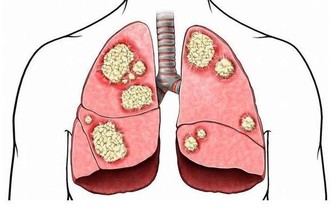

心臟病是全世界的頭號死亡原因,所以任何人都要了解它的風險性,

因為,患有糖尿病的成年人死於心臟病的可能性,是沒有心臟病的成年人的兩到四倍。

雖然心臟病和糖尿病似乎不相關,但實際上有幾個重疊的原因和症狀。

而且,糖尿病是“擊潰血管的最後一根稻草”,當一個人在高血壓或膽固醇升高的情況下出現高血糖時,就像在原本已經脆弱不堪的血管上火上加油,這導致血管更加狹窄。